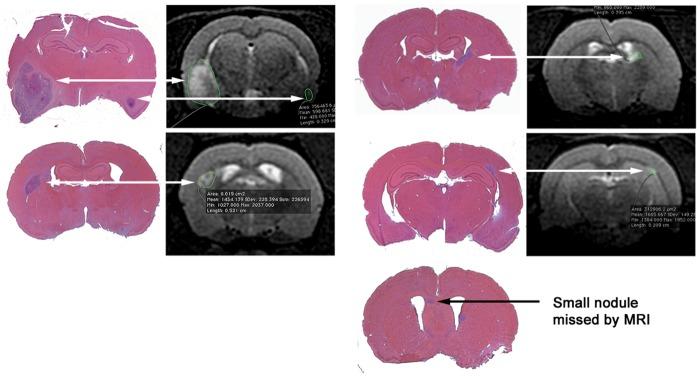

Rats treated in utero with N-ethyl-N-nitrosourea began to die of brain tumors from approximately 120 days of age. We delivered a single dose of whole brain irradiation (20 Gy) on day 115 of age, began treatment with NOX-A12 immediately following irradiation, and continued with either 5 or 20 mg/kg for 4 or 8 weeks, doses and times equivalent to well-tolerated human exposures. We found a marked prolongation of rat life span that was dependent on both drug dose and duration of treatment. In addition we treated tumors only when they were visible by MRI and demonstrated complete regression of the tumors that was not achieved by irradiation alone or with the addition of temozolomide.

在子宫内用 N-乙基-N-亚硝脲处理的大鼠从大约 120 天开始死于脑肿瘤。我们在 115 天大时给予单次全脑照射(20 Gy),在照射后立即开始给予 NOX-A12 治疗,并继续给予 5 或 20 mg/kg 的剂量 4 或 8 周,剂量和时间相当于可耐受的人体暴露量。我们发现大鼠的寿命明显延长,这取决于药物剂量和治疗持续时间。此外,我们仅在 MRI 可见肿瘤时进行治疗,并证明了肿瘤的完全消退,这是单独照射或添加替莫唑胺无法实现的。